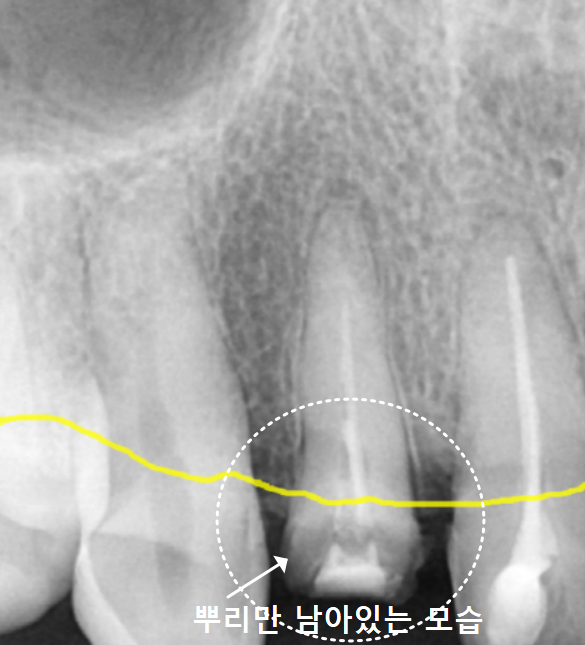

240831 뿌리만 남은 앞니

240831